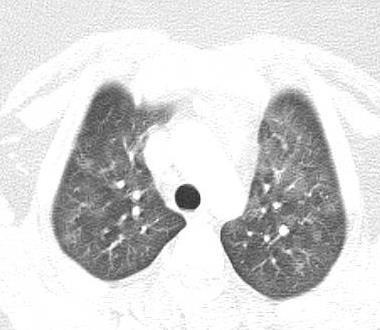

Pediatric COVID-19

OUTCOME

Imaging of Covid 19 infection in children